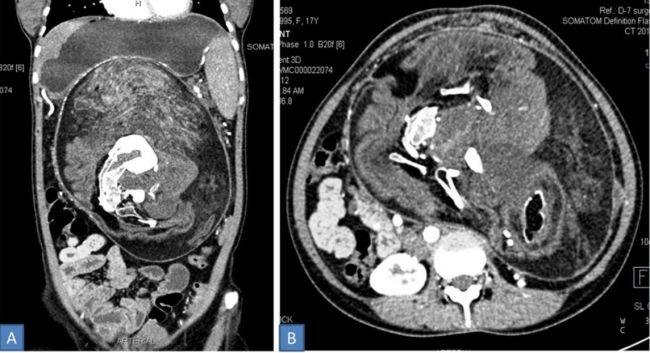

Thiếu nữ 17 tuổi nói với các bác sĩ rằng cô luôn cảm thấy no và chướng bụng dù không ăn nhiều. Hình ảnh chụp CT cho thấy bên trong ổ bụng của cô gái chứa nhiều xương có hình dạng giống “đốt sống, xương sườn”. Các bác sĩ chẩn đoán thiếu nữ gặp phải tình trạng bào thai trong bào thai, hay còn được gọi là Fetus-in-fetu.

| Hình ảnh CT ổ bụng của cô gái 17 tuổi. Ảnh: Live Science. |